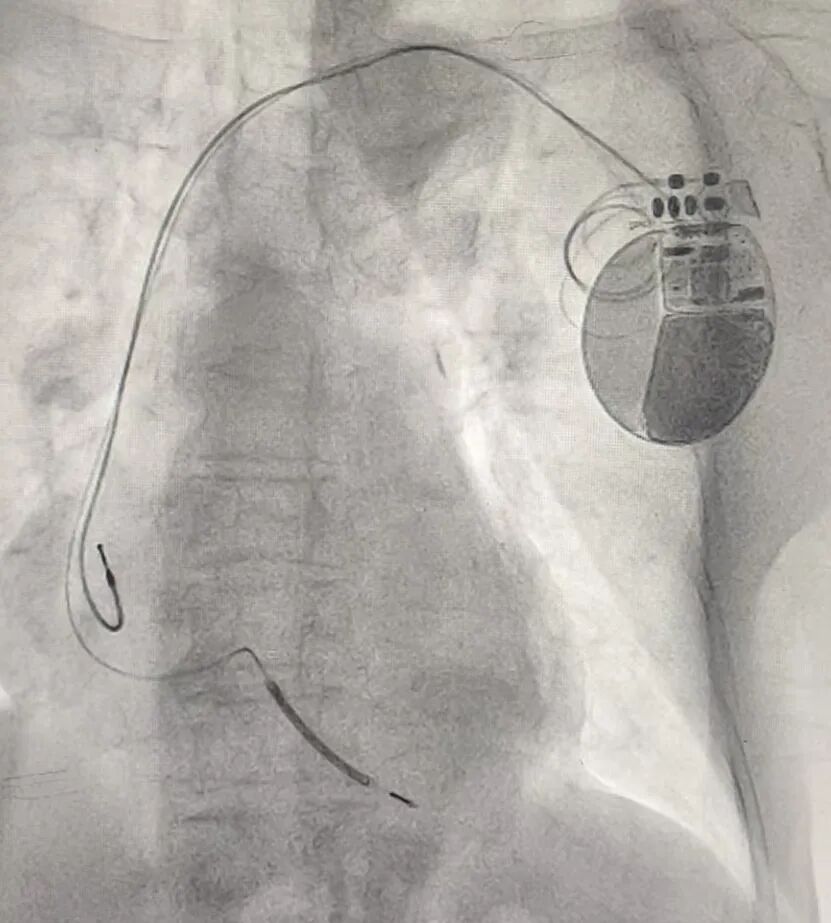

近日,滨州市中心医院入住一名90岁的突发晕厥的老人,心血管内科一病区孙桂芳主任团队详细检查评估后,诊断为“室性心动过速”。结合患者身体状况,经充分讨论后,为其植入ICD治疗。

手术过程顺利,术后ICD功能监测各项指标正常,患者未再发作晕厥,现已康复出院,ICD给这位老人带来“心生”。该例ICD植入患者为医院首例,在全市范围内如此高龄患者成功植入ICD也较为罕见。

ICD是一种植入体内的小型电子医疗设备,植入在胸部皮下,电极导线连接到心脏,主要用于监测心脏节律,并检测到威胁生命的恶性心律失常(如室颤、室性心动过速等)时,通过起搏或电击的方式恢复正常心律,从而预防心脏性猝死。